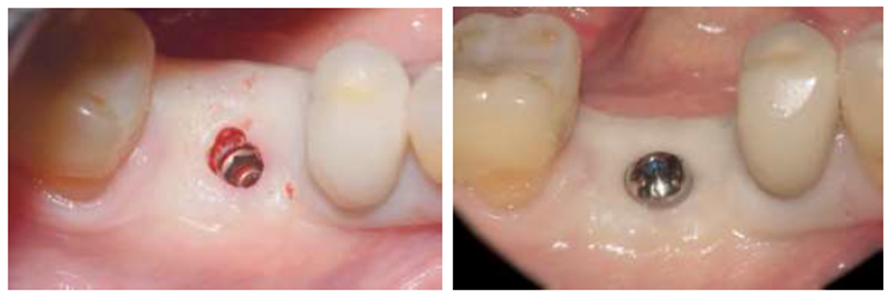

O implante foi inserido com o motor cirúrgico até a visualização do travamento em 46 Ncm, com a sua inserção final concluída através da catraca cirúrgica ao atingir o torque de inserção de 60 Ncm. Finalmente, o leito cirúrgico foi fechado com sutura utilizando fio de seda (Figuras 10 a 15). Após seis meses da inserção do implante, a reabertura cirúrgica foi realizada com a técnica de punção com broca cilíndrica diamantada, seguida pela colocação do cicatrizador (Figuras 16 e 17).